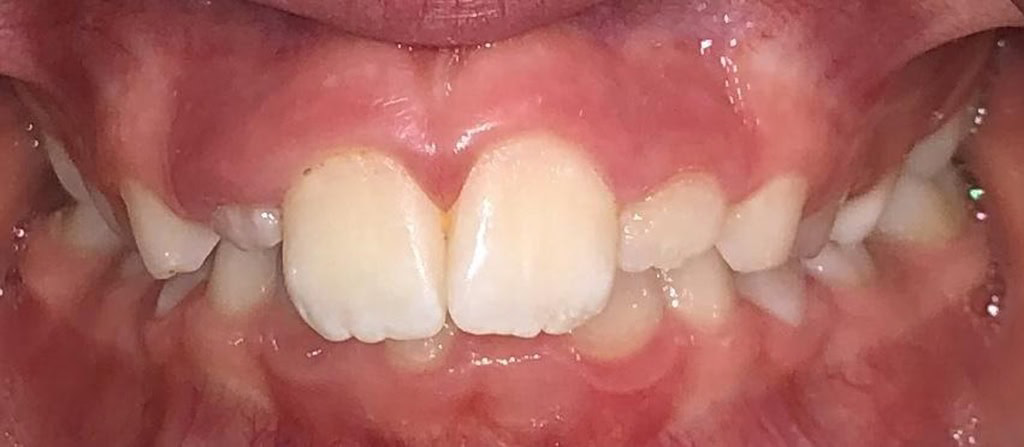

Actual Patient: Casen

Casen Before 6 Casen After 6

Severe crowding, Severe Deep Bite with trauma, Narrow Jaws

img Actual Patient Casen before 1 img Actual Patient Casen after 1

Before

After